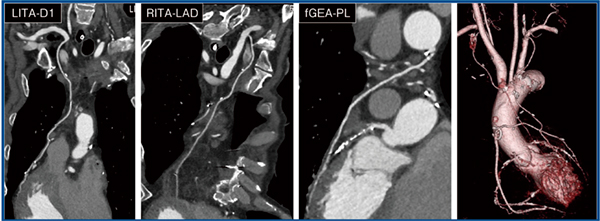

また,Aquilion ONE / INSIGHT Editionでは,160列での高速ヘリカル撮影(0.24s/rot,HP:215)によって,成人男性の体幹(胸部〜骨盤)を2〜2.5秒で撮影可能である。図3は冠動脈バイパス術(CABG)後評価目的のCT angiography(CTA)である。従命・息止め困難なため心電図非同期での高速ヘリカル撮影を行ったところ,CABGルートをほぼブレなく撮影可能であった。従来CTで同等の画像を取得するのは困難と思われ,Aquilion ONE / INSIGHT Editionの威力を実感した一例である。

図3 CABG後評価目的のCTA